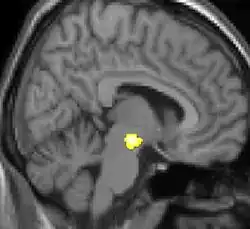

Voxel-based morphometry is a computational approach to neuroanatomy that measures differences in local concentrations of brain tissue, through a voxel-wise comparison of multiple brain images.[1][2] In traditional morphometry, volume of the whole brain or its subparts is measured by drawing regions of interest (ROIs) on images from brain scanning and calculating the volume enclosed. However, this is time consuming and can only provide measures of rather large areas. Smaller differences in volume may be overlooked. The value of VBM is that it allows for comprehensive measurement of differences, not just in specific structures, but throughout the entire brain. VBM registers every brain to a template, which gets rid of most of the large differences in brain anatomy among people. Then the brain images are smoothed so that each voxel represents the average of itself and its neighbors. Finally, the image volume is compared across brains at every voxel.

One of the first VBM studies and one that came to attention in mainstream media was a study on the hippocampus brain structure of London taxicab drivers.[7] The VBM analysis showed the back part of the posterior hippocampus was on average larger in the taxi drivers compared to control subjects while the anterior hippocampus was smaller. London taxi drivers need good spatial navigational skills and scientists have usually associated hippocampus with this particular skill.